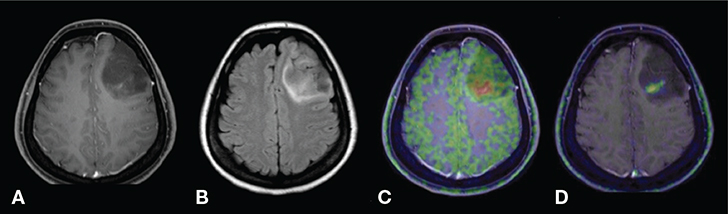

Fig 4

Figure 4. T1-weighted post-contrast (A), FLAIR (fluid-attenuated inversion recovery; B), 11C-MET PET (C) and 18F-FACBC PET (D) images of a patient with diffuse astrocytoma, WHO grade II, IDH mutated. The conventional MR images show a poorly enhancing lesion with some high signal surrounding the lesion. Although increased PET agent uptake can be seen in a small part of the tumor on both the 11C-MET and 18F-FACBC PET images, this case also illustrates the relatively high uptake of the natural amino acid-based 11C-MET in the healthy brain parenchyma compared to the unnatural amino-acid based 18F-FACBC which can result in decreased T/N ratios. This figure is reproduced – with new figure legend appropriate for current book chapter – from Tsuyuguchi et al. (2017), Figure 1 Case 1, under the terms of the Creative Commons Attribution License (http://creativecommons.org/licenses/by/3.0) (80).